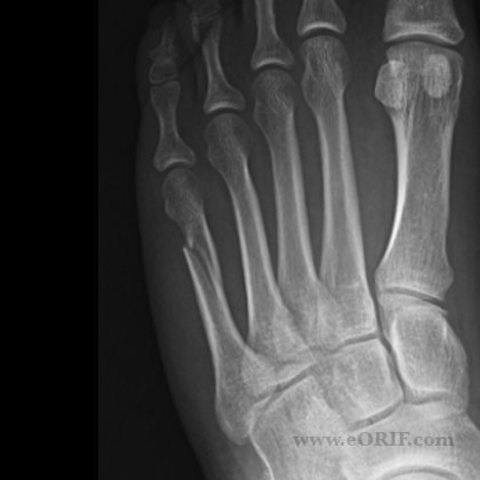

• Broke my left metatarsal

Broke my left metatarsal

Fractured a bone in my foot playing soccer in 8th grade.